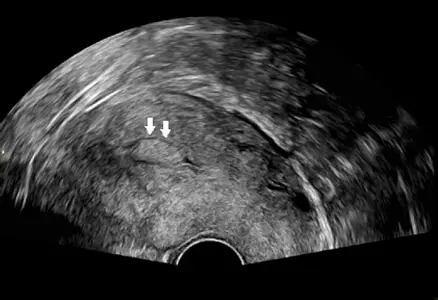

影像分析:

- 檢查時機:題目說明檢查是在「經期剛結束」時進行。這是進行婦科超音波評估子宮內膜病灶的最佳時機(Early Proliferative Phase),因為此時正常的子宮內膜最薄,任何突出的病灶都會因為對比而被清楚顯示。

- 影像特徵:

- 這是一張**經陰道超音波(Transvaginal Ultrasound, TVUS)**的子宮矢狀切面圖(Sagittal view)。

- 影像中央可見子宮本體,箭頭所指處位於子宮腔內(Endometrial cavity)。

- 病灶呈現為一個**邊界清晰、高回音(Hyperechoic,偏亮白)**的橢圓形腫塊。

- 該腫塊位於兩層子宮內膜之間,明顯突出於子宮腔內,且周圍有一圈低回音的暈圈(可能是微量子宮腔積液或內膜介面),這是典型的子宮內膜息肉影像特徵。

- 並未觀察到子宮肌肉層(Myometrium)有明顯的低回音腫塊或陰影,故較不像是位於肌肉層內的肌瘤。

- 影像特徵:典型的超音波表現為子宮腔內的高回音(Hyperechoic)病灶,且常保留原本的內膜輪廓。在經期剛結束、內膜變薄時最容易被發現。

病人表現為間斷性出血及經期延長,這是子宮內膜息肉的典型症狀(屬於 AUB-P)。超音波選在經期結束後進行,影像清楚顯示子宮腔內有一個**高回音(Hyperechoic)**的團塊。相比之下,肌瘤通常較暗(低回音)且位於肌肉層;子宮頸糜爛需內診診斷;畸胎瘤位於卵巢。因此,最可能的診斷為 D. 子宮內膜息肉。